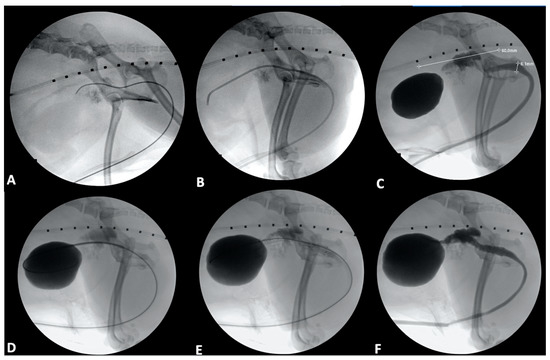

4.1. Ureter

4.2. Urethra